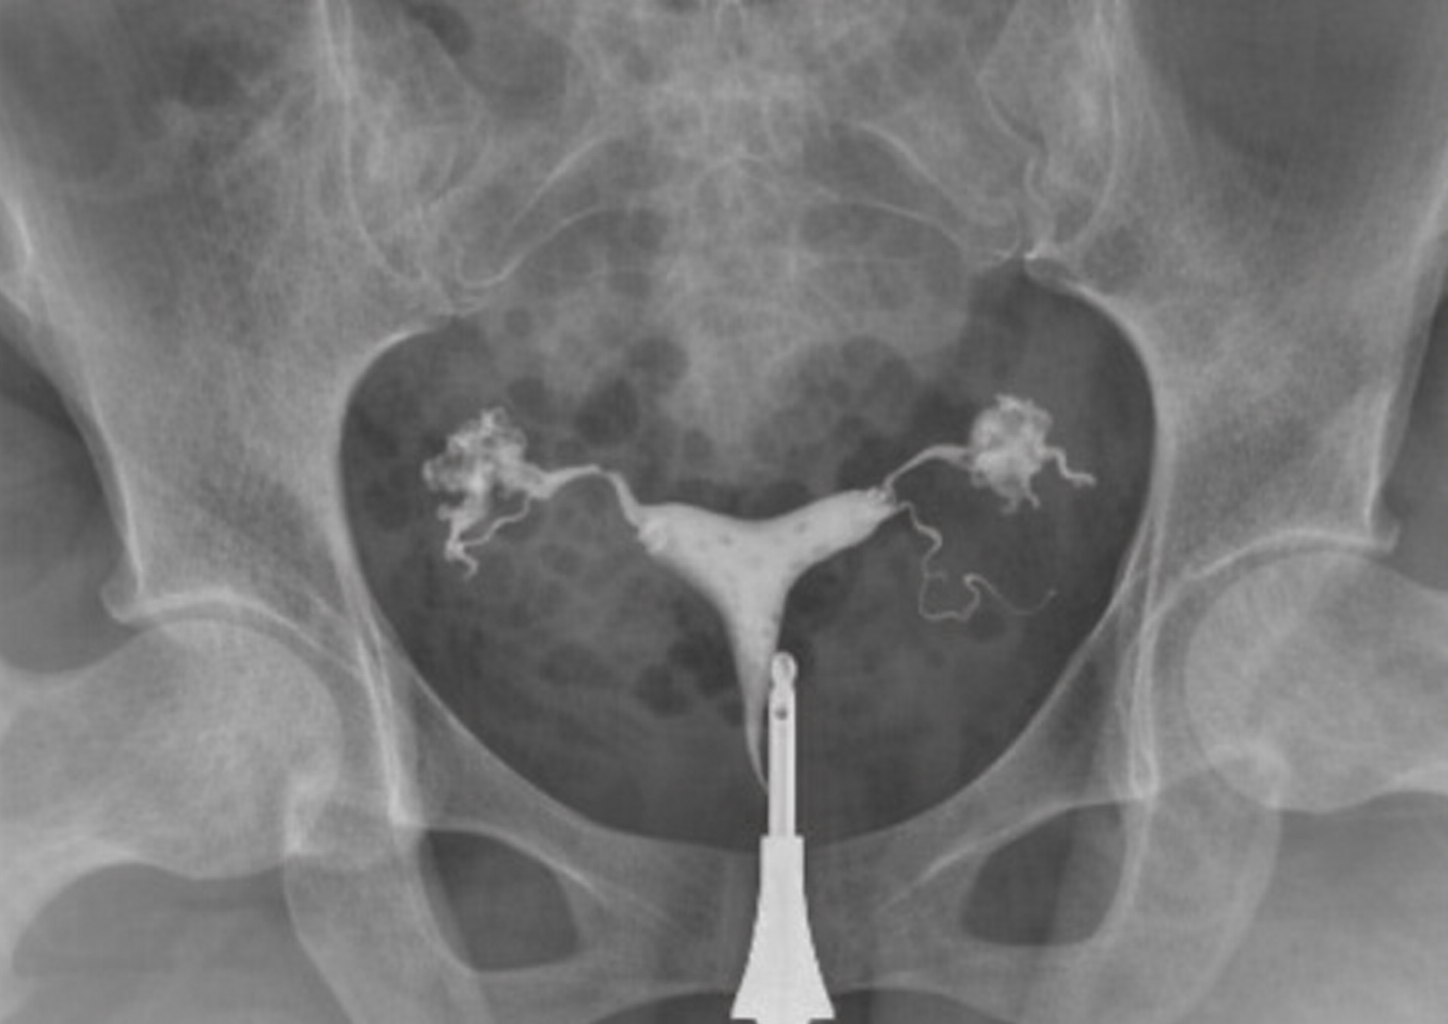

Hydrosalpinx ist ein Zustand, bei dem sich die Eileiter mit Flüssigkeit füllen. Er entsteht in der Regel infolge von durchgemachten Infektionen, entzündlichen Erkrankungen des Beckens oder Schädigungen der Eileiter. Dieser Zustand kann die normale Funktion der Eileiter beeinträchtigen und die Entstehung einer Schwangerschaft erschweren.

Bei Vorliegen eines Hydrosalpinx kann die in den Eileitern angesammelte Flüssigkeit gelegentlich in die Gebärmutter zurückfließen. Diese Flüssigkeit kann die Einnistung des Embryos in die Gebärmutterwand verhindern und insbesondere bei IVF-Behandlungen die Erfolgsrate erheblich verringern. Daher ist die Behandlungsplanung bei Patientinnen mit diagnostiziertem Hydrosalpinx von großer Bedeutung.